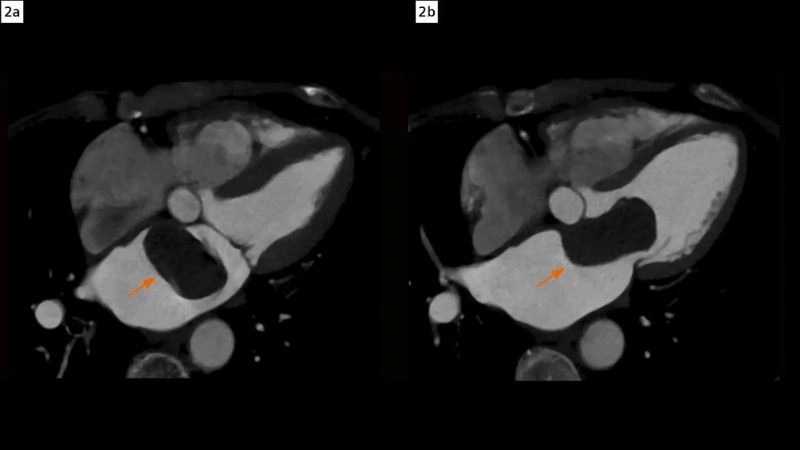

Cardiac myxoma (heart tumor) is a rare benign tumor usually found in the left atrium of the heart. Visual examples show its mass obstructing blood flow and altering cardiac function.

Myxoma vs thrombus differences between tumor and clot